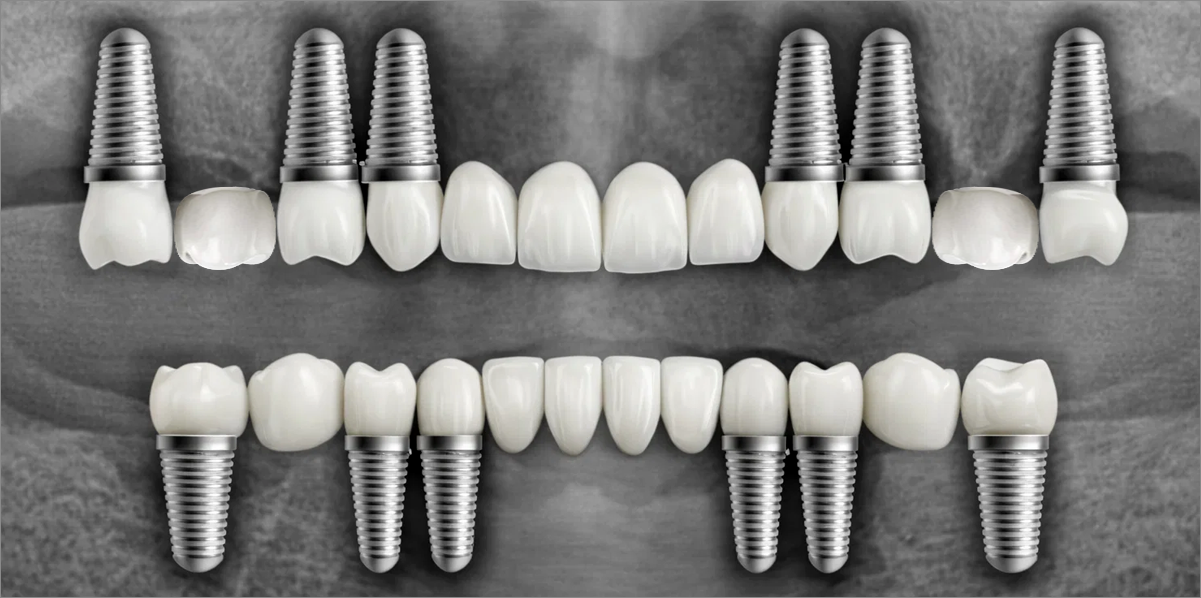

전체 임플란트

위 아래 치아가 정확하게 맞아야하는 고난이도 임플란트

임상 경험이 많은 숙련된 전문의의 섬세한 기술력이 중요합니다.

3D 디지털 진단을 통한 체계적인 계획

전체 임플란트는 위턱과 아래턱의 교합, 잇몸뼈의 상태 및

얼굴 변화 등 모든 것을 고려해 식립해야 합니다.

서울더자연치과는 3D 디지털 기술의 정밀 진단을 바탕으로

수술 계획을 세워 수술을 집도합니다.